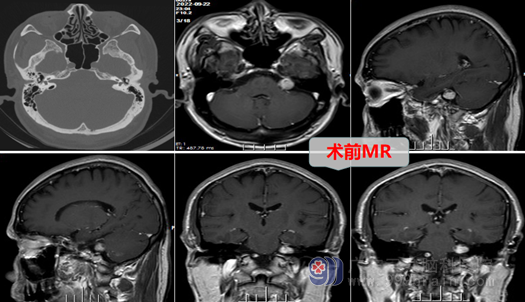

住院检查后的,经外十科团队诊治,何大叔被确诊为左侧桥小脑角区占位病变:听神经瘤。听神经瘤准确地说是前庭神经鞘瘤,是前庭神经靠近内听道生长的良性肿瘤,它压迫耳蜗神经引起耳鸣及听力下降,前庭神经肿瘤本身可引起头晕,如果肿瘤继续长大还会引起面瘫等症状;这类肿瘤都要通过精准的显微神经外科手术方式进行治疗,何大叔症状已有两年,且呈逐渐加重的趋势,应尽进行手术,否则,很容易出现面瘫甚至后组颅神经及脑干损伤的并发症和后遗症。

外十科团队对何大叔制定了严密的手术方案:双镜(显微镜及神经内镜)结合及神经电生理监测下前庭神经鞘瘤切除术。主管医生向何大叔及其家属讲解病情后取得了手术同意,手术当日由外十科主任欧阳辉教授主刀,在全麻下为何大叔进行精细的左侧桥小脑角占位性病变切除术,整个手术过程顺利,肿瘤被全部切除,患者的面神经、耳蜗神经都保存良好,后组颅神经、三叉神经、脑干等也未受到任何损伤,术后的何大叔恢复良好:没有面瘫,没有出现吞咽困难等。